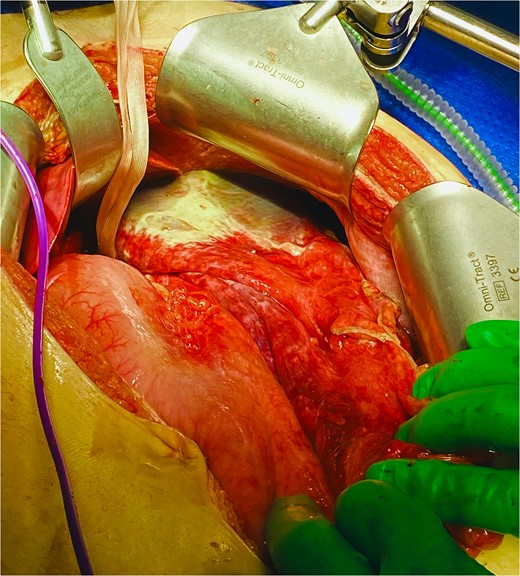

He was expedited to theatre, commencing with gastroscopy to exclude an intraluminal mechanical obstruction. There was widespread mucosal ulceration and necrosis (Figs 4–7) necessitating a laparotomy and assessment for transmural necrosis. The stomach was globally ischaemic with gangrene at the fundus (Figs 8–10) and hence a total gastrectomy was performed and reconstructed with roux-en-y oesophagojejunostomy and jejunojejunostomy.

Total gastrectomy specimen showing areas of gangrene and necrosis.